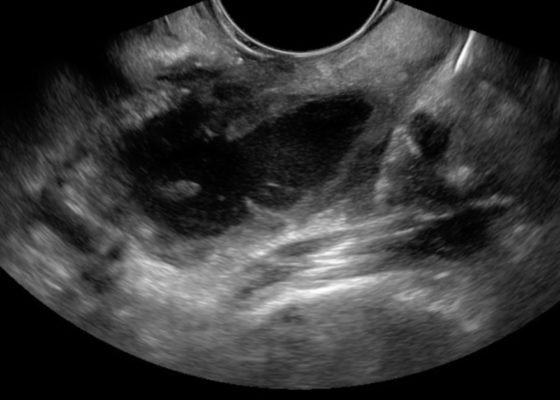

Bedside Ultrasound for the Diagnosis of Peritonsillar Abscess

DOI: https://doi.org/10.21980/J8N33NThe first video is an intraoral ultrasound using the high frequency endocavitary probe demonstrating an anechoic fluid collection adjacent to the patient’s enlarged left tonsil. The second video shows real-time ultrasound-guided successful drainage of the PTA.